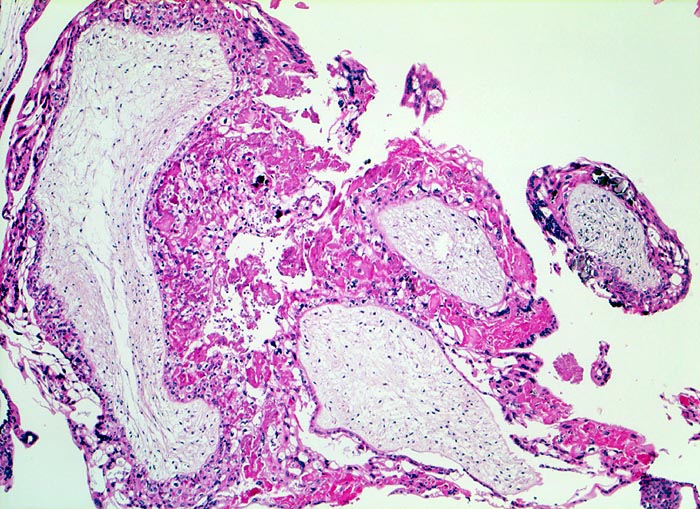

Blasenmole

Gefässfreie blasig aufgetriebene Villi bedeckt von zirkulär proliferiertem Trophoblastepithel.

beta HCG Level von 150'000 mIU/mL. Uterus zu gross für das Gestationsalter von 10 Wochen. Arterielle Hypertonie.

Histologie

50